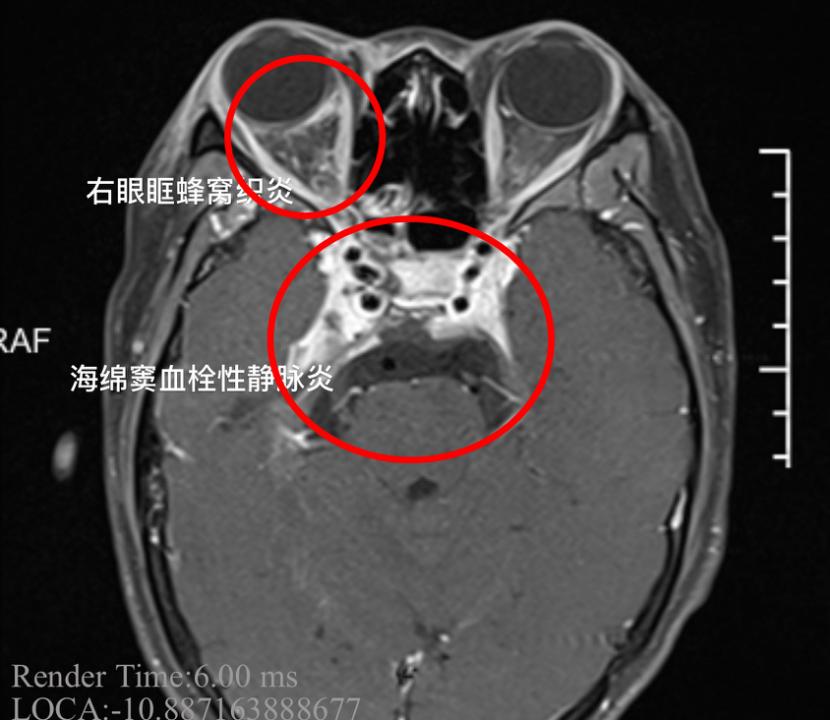

经过诊断,小杨患上了“海绵窦血栓性静脉炎”,这是一种严重的颅内感染。这种病如果没有得到及时治疗,可导致患者死亡。

医院接诊的神经内一科副主任医师韩锟说:“患者刚来的时候,病情是比较严重的,体温持续在39℃以上,女孩的右眼外凸,眼球已经固定无法转动,瞳孔扩大,对光反射消失,多组颅神经受损,这都是海绵窦严重感染的征象,同时我们发现患者的脑膜刺激成阳性,海绵窦的炎症已经扩散,出现了脑膜炎,继续进展随时有生命危险。”